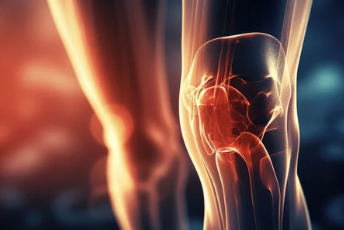

무릎 연골 손상은 연골이 닳거나 손상되어 발생하는 질환입니다. 연골은 무릎 관절을 매끄럽게 움직이도록 하는 역할을 하며, 연골이 손상되면 통증, 붓기, 움직임 제한 등의 증상이 나타납니다. 오늘은 무릎 연골 손상 증상 및 연골주사 효과, 부작용, 수술비용 등 다양한 정보를 알려드리겠습니다.

무릎 관절은 우리 몸에서 가장 큰 관절이며, 걷기, 뛰기, 앉기 등 다양한 활동을 수행하는 데 중요한 역할을 합니다. 무릎 관절의 표면을 덮고 있는 연골은 매끄럽고 탄력적이며, 뼈와 뼈가 서로 마찰 없이 부드럽게 움직일 수 있도록 도와줍니다. 하지만 이 연골이 손상되면 무릎 통증, 움직임 제한, 불안정성 등의 문제가 발생할 수 있습니다.